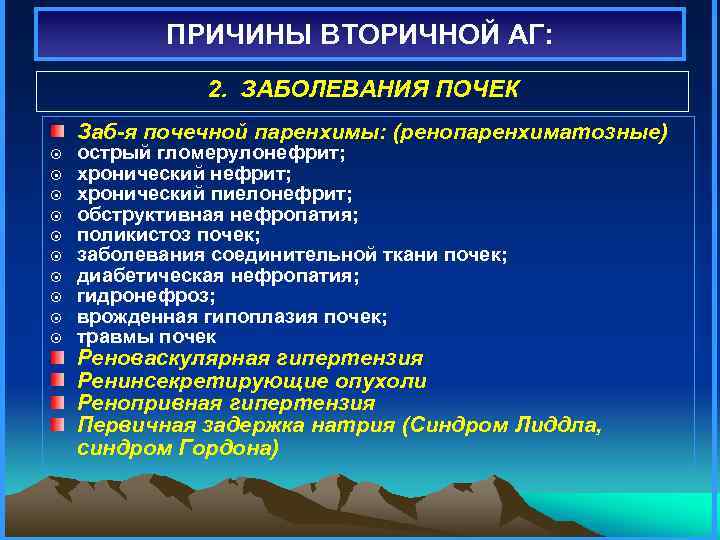

ПРИЧИНЫ ВТОРИЧНОЙ АГ: 2. ЗАБОЛЕВАНИЯ ПОЧЕК Заб-я почечной паренхимы: (ренопаренхиматозные) ¤ ¤ ¤ ¤ ¤ острый гломерулонефрит; хронический пиелонефрит; обструктивная нефропатия; поликистоз почек; заболевания соединительной ткани почек; диабетическая нефропатия; гидронефроз; врожденная гипоплазия почек; травмы почек Реноваскулярная гипертензия Ренинсекретирующие опухоли Ренопривная гипертензия Первичная задержка натрия (Синдром Лиддла, синдром Гордона)

ПРИЧИНЫ ВТОРИЧНОЙ АГ: 2. ЗАБОЛЕВАНИЯ ПОЧЕК Заб-я почечной паренхимы: (ренопаренхиматозные) ¤ ¤ ¤ ¤ ¤ острый гломерулонефрит; хронический пиелонефрит; обструктивная нефропатия; поликистоз почек; заболевания соединительной ткани почек; диабетическая нефропатия; гидронефроз; врожденная гипоплазия почек; травмы почек Реноваскулярная гипертензия Ренинсекретирующие опухоли Ренопривная гипертензия Первичная задержка натрия (Синдром Лиддла, синдром Гордона)